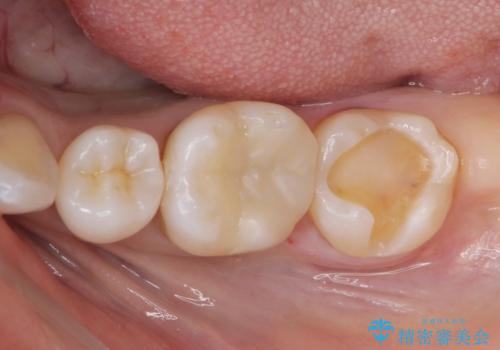

虫歯が再発していたので拡大鏡下で取り切った後、e-maxインレーにて治療しました。

また、一番奥の歯も古い樹脂の治療がされていたため虫歯の予防のために樹脂を取り除き、う蝕がないことを確認してe-maxインレーで治療しました。

- e-maxインレー 7.7万円 ×2本費用は治療当時の料金となります

e-max(セラミック)は歯質との隙間が出来にくく虫歯の再発のリスクが低くなります。